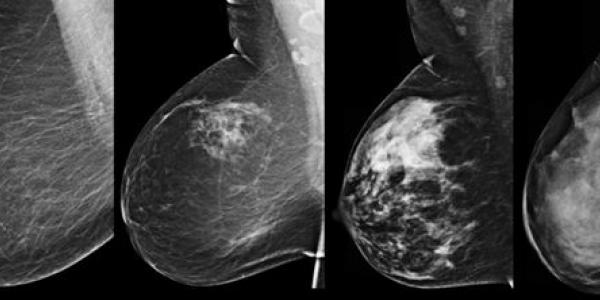

En el estudio, llevado a cabo en Barcelona, han colaborado hasta 45 centros de investigación de distintos países europeos. Se trata del primer estudio dirigido a pacientes con cáncer de mama HER2-positivo.

Un nuevo tratamiento contra el cáncer de mama, que aún esta en fase de ensayos, puede traer esperanzas para seguir con la lucha y acabar con la enfermedad.